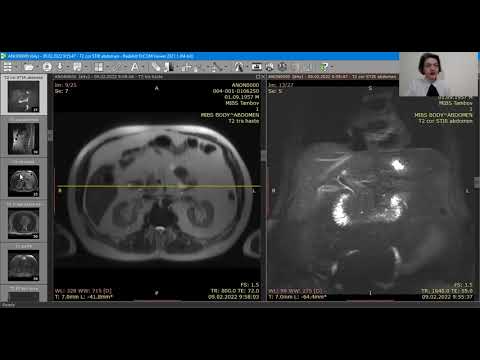

МРТ в диагностике желчекаменной болезни